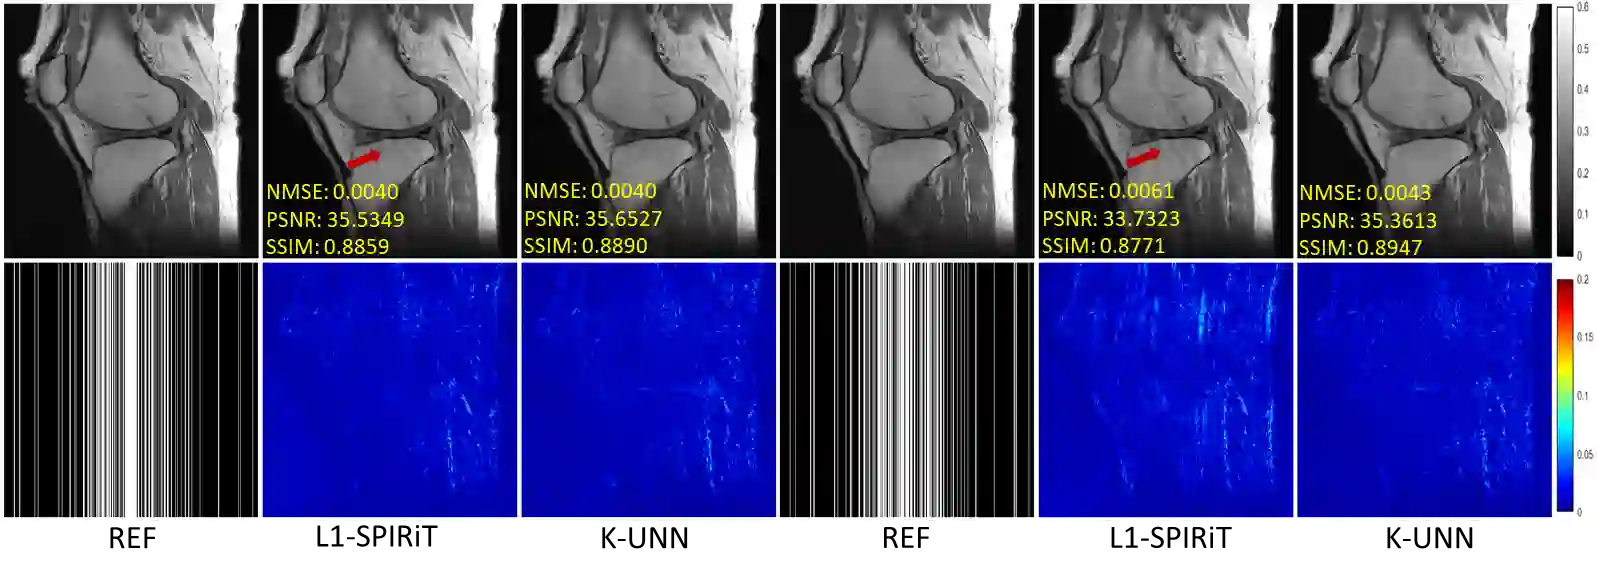

Recently, untrained neural networks (UNNs) have shown satisfactory performances for MR image reconstruction on random sampling trajectories without using additional full-sampled training data. However, the existing UNN-based approach does not fully use the MR image physical priors, resulting in poor performance in some common scenarios (e.g., partial Fourier, regular sampling, etc.) and the lack of theoretical guarantees for reconstruction accuracy. To bridge this gap, we propose a safeguarded k-space interpolation method for MRI using a specially designed UNN with a tripled architecture driven by three physical priors of the MR images (or k-space data), including sparsity, coil sensitivity smoothness, and phase smoothness. We also prove that the proposed method guarantees tight bounds for interpolated k-space data accuracy. Finally, ablation experiments show that the proposed method can more accurately characterize the physical priors of MR images than existing traditional methods. Additionally, under a series of commonly used sampling trajectories, experiments also show that the proposed method consistently outperforms traditional parallel imaging methods and existing UNNs, and even outperforms the state-of-the-art supervised-trained k-space deep learning methods in some cases.